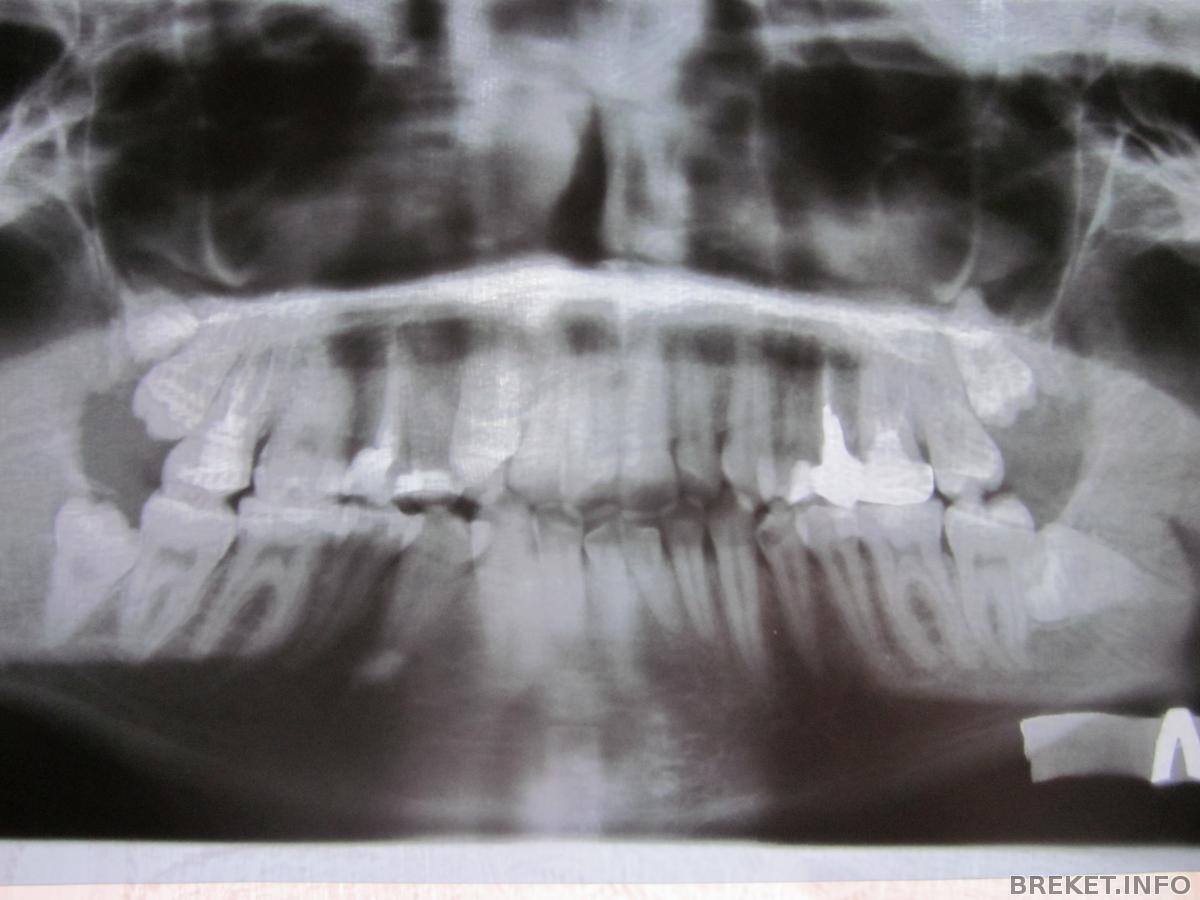

а еще я очень боюсь удалять зубы мудрости. у меня их 5 штук((( с правой стороны вверху один вылез, а другой в десне. вот полюбуйтесь

пс. 5 мудростей??? впервые слышу.. (сорри второй раз, Маргариита тоже с пятью))))) может доктор перепутал 7-ки. или у некоторых бывает и в помине не было 6ок.. сейчас есть такая аномалия.

Viccu, спасибо за развернутый ответ))) терапевт моя и рентгенолог говорят, что это два зуба мудрости на одной стороне. посмотрим, что ортодонт скажет)